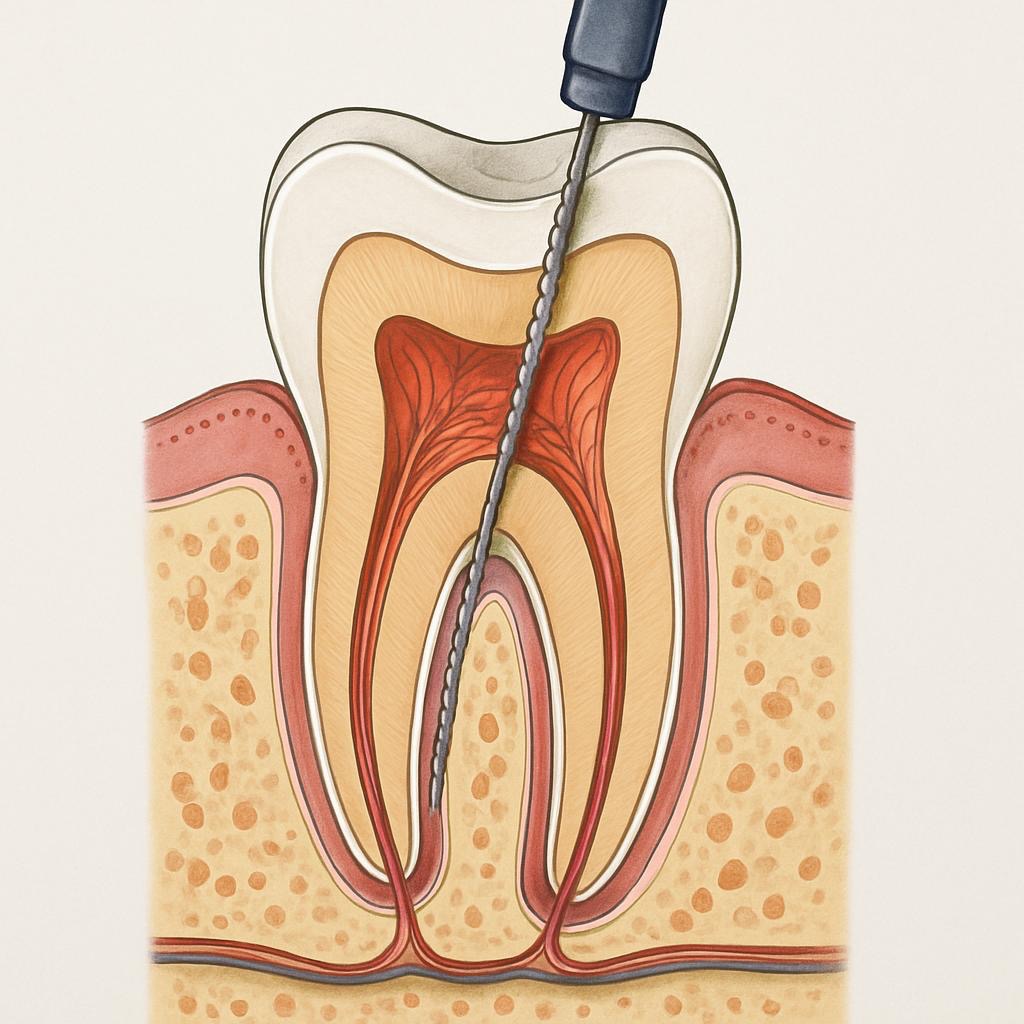

Canal

Procedimento indicado quando o dente esta inflamado ou infectado. Consiste na remoção do tecido comprometido.